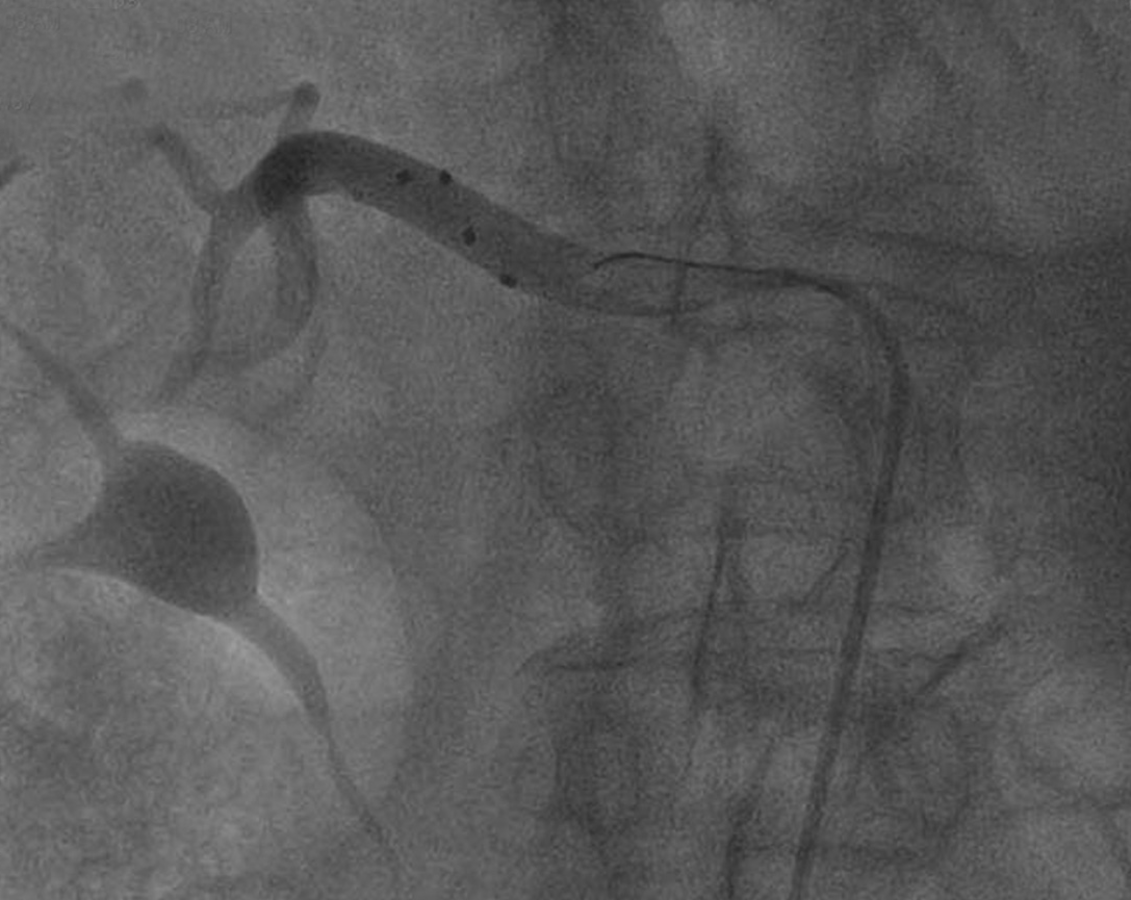

Die in der Praxis gemessenen systolischen Blutdruckwerte lagen zwischen 150 und 180 mmHg, die diastolischen bei mindestens 90 mmHg. In der 24-Stunden-Messung musste der systolische Wert zwischen 140 und 170 mmHg betragen und die Patienten mussten seit mindestens sechs Wochen auf ein bis drei blutdrucksenkende Medikamente in stabilen Dosierungen eingestellt sein. Die Teilnehmer unterzogen sich alle einer Angiographie, anschließend erhielten sie randomisiert entweder eine renale Denervierung (RDN) mittels Radiofrequenzablation oder eine Scheinbehandlung. Primärer Endpunkt war die Veränderung der Blutdruckwerte. Anhand von Bluttests überprüften die Untersucher, wie zuverlässig die Antihypertensiva­einnahme erfolgte.

Radiofrequenz­ablation in Aktion: Die schwarzen Punkte sind die vier Elektroden. Radiofrequenz­ablation in Aktion: Die schwarzen Punkte sind die vier Elektroden. © Medtronic GmbH